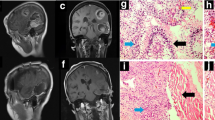

Next, we tested if the treatment with SANPs 1-(2)Tf Praja2 (SANPs-siPraja2 in the following part of the text and figures) inhibits GBM in vivo. U87MG cells were stereotaxically implanted in the left caudate nucleus of the mouse brain. At 1-week post-implantation, mice bearing orthotopic GBM lesions were perfused every two days with either SANPs-siPraja2 or SANPs-siRNAc. Three weeks after the first SANPs perfusion, mice were sacrificed, and brain lesions were analyzed. As shown in Fig. 6c, d, treatment with SANPs-siPraja2 significantly reduced the tumor volume, compared to controls (SANPs-siRNAc). Hematoxylin/eosin staining showed a GBM cell population with a pleomorphic volume and morphology; the nuclei appeared voluminous, vesicular, and compacted, showing condensed nuclear chromatin with a prominent nucleolus (Fig. 6e). Cells were arranged in mutual contact in a disordered fashion, but they were devoid of cohesion. The more relevant histologic difference between tumor lesions of both experimental groups was a significant reduction of cells in tumor sections of SANPs-siPraja2-treated mice, compared to controls. A notable reduction of the proliferation marker Ki67 in tumor sections from SANPs-siPraja2-treated mice was also evident (Fig. 6e, f).

a Schematic view of the experimental procedures. U87MG cells were stereotaxically implanted into the brain of nude mice (time 0). One week post-implantation, SANPs-siRNAs were i.v. injected into the caudal vein every 48 h, for a total of 14 days of treatment. At 3 weeks post-implantation, mice were sacrificed and tumor lesions isolated and further characterized. b Brain distribution of rhodamine-labeled SANPs-siPraja2 by fluorescence analysis at 9 h after i.v. injection. GBM lesions were identified by immunostaining the same brain sections with an anti-human vimentin antibody. Nuclei were stained with DAPI. Representative images are shown. Scale bar, 50 μm. c Tissue sections from tumor lesions were stained with hematoxylin/eosin. d Quantitative analysis of the tumor volume is expressed as a mean value ± SEM. Three independent experiments were performed. P value: ** = 0.0014. e Tumor sections were stained with hematoxylin/eosin or immunostained for Ki-67. Scale bar, 50 μm. f Quantitative analysis of Ki-67-positive cells in tumor lesions from control and SANPs-siPraja2 treated mice. The data were expressed as a mean value ± SEM from three independent experiments. P value: ** = 0.0055. g U87MG-Luc cells were injected into the brain of 6 weeks old CD1 mice. Three hours following implantation, bioluminescent intensity (BLI) was measured by intraperitoneal injection of 150 mg/kg d-Luciferin potassium salt. At 1-week post-injection, based on BLI measurement, mice were randomized into two experimental groups of 12 animals, and each group was treated by tail vein injection with SANPs-siPraja2 (GP1) and SANPs-siRNAc (GP2), respectively. Treatments were repeated twice a week for 4 weeks, then four mice for each group were sacrificed and organs collected. BLI analysis was performed every week and quantitative data were collected. A representative set of animals for each experimental group is shown. h Quantitative and cumulative analysis of BLI scores. *** <0.001. i Kaplan–Meier curve of treated animals. At 52 days from U87MG implantation, all the animals from SANPs-siRNAc group died. In contrast, about 40% of SANPs-siPraja2 mice were still healthy, but the experiment was terminated in accordance with Authorities guidelines. j Immunostaining analysis for praja2, KSR2, pThr172-AMPKα, and AMPKα1 in tumor sections from control and SANPs-siPraja2 treated mice. Scale bar, 50 μm.